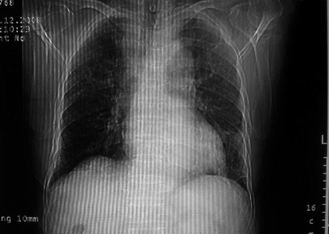

男,78岁,咳嗽、咳痰、发热入院,抗炎治疗一周后已退热,咳血似痰。

10月3日片:

10月9日片: